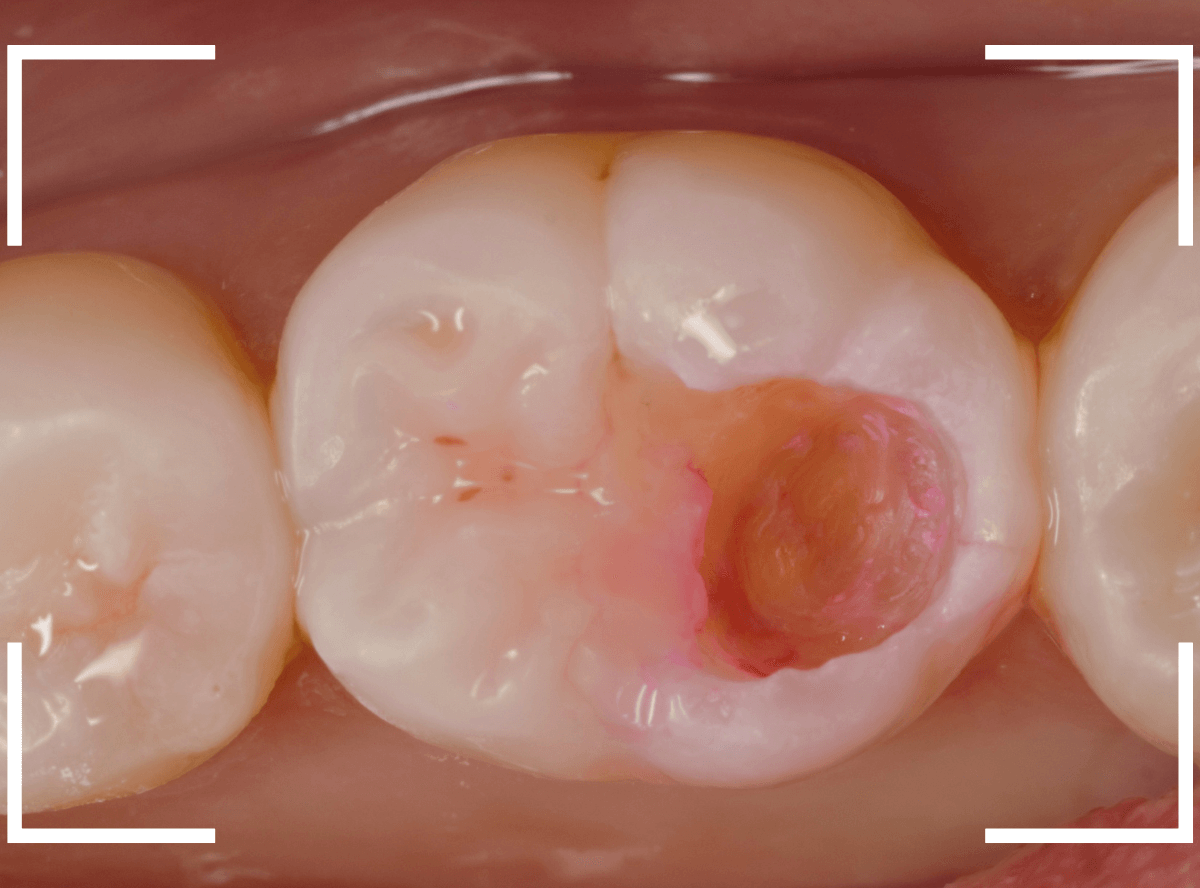

Case.20 劣化したレジン側面から進行した虫歯

「つめものが欠けたまま長期間放置して、歯がしみる」という訴えで来院された患者さんさんです。

拝見すると、劣化したレジンが欠けて、中で虫歯になっているのがわかります。

・欠けたまま長期間放置した

・しみるという自覚症状がある

事から、中で深い虫歯になっている事が想像されます。

レジンを外しながら、虫歯を確認します。

慎重にレジンを除去しましたが、途中で露髄(神経が露出する事)しました。

歯の神経の中には、血管も含まれているので、神経が露出すると、このように出血します。

「しみる、痛い」などの明確な強い症状がある場合、このような状況の事が多いです。

今回は出血量が多く、神経を除去する治療(抜髄)の可能性が高いとも感じましたが、できる限り神経を保存する方法を取ることにしました。

神経を保護するお薬をつめて蓋をしてしばらく経過観察します。

神経を除去すると、治療期間が長引くうえに、歯の寿命がとても短くなってしまいます。

できるだけ歯の神経を残すためには、症状が出てからの歯科受診ではなく、定期的なメンテンナンス受診を続けるようにしてください。